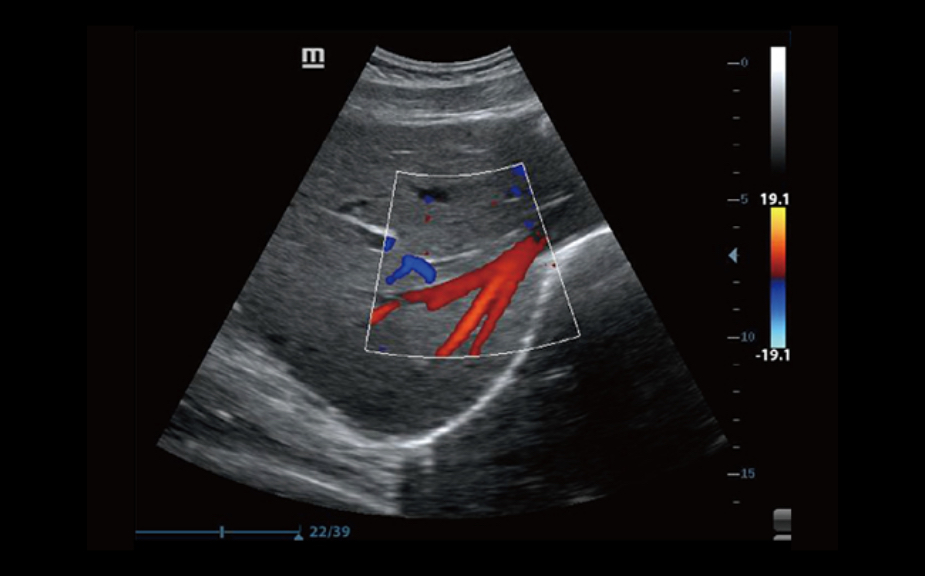

3B/4B G?rÞntÞleme

G?rÞntÞnÞn her y?nden h?zl? ve kolay bir ?ekilde izlenebilmesini sa?layan 3B/4B ?evirme ve E?itleme ?zelli?i ile